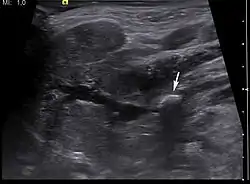

The stone seen in the submandibular duct on the persons right side

Diagnosis is usually made by characteristic history and physical examination. Diagnosis can be confirmed by x-ray (80% of salivary gland calculi are visible on x-ray), by sialogram, or by ultrasound.